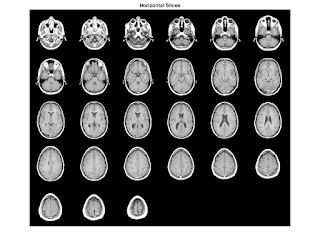

example to display MRI image and data

close all; % Clear all windows clear all; % Clear all variables clc; % Clear console % load the data and transform the data array from 4-D to 3-D % The MRI data, D, is stored as a 128-by-128-by-1-by-27 array. % Use the squeeze command to remove 4-D to 3-D. % The result is a 128-by-128-by-27 array load mri D = squeeze(D);

display one of the MRI images

figure

colormap(map)

image_num = 10;

image(D(:,:,image_num))

axis image

x = xlim;

y = ylim;

2-D Contour Slice

contour plot uses the jet colormaptwodc = brighten(jet(length(map)),-.5);

figure;

colormap(twodc);

contourslice(D,[],[],image_num)

axis ij

xlim(x)

ylim(y)

daspect([1,1,1])

%%3-D Contour Slices figure colormap(twodc) contourslice(D,[],[],[1,12,19,27],10); view(3); axis tight

Slices 3-Dimensional MRI Data

load mri;%Load the MRI data figure; montage(D,map) %view the 27 horizontal slices as a montage. title('Horizontal Slices');